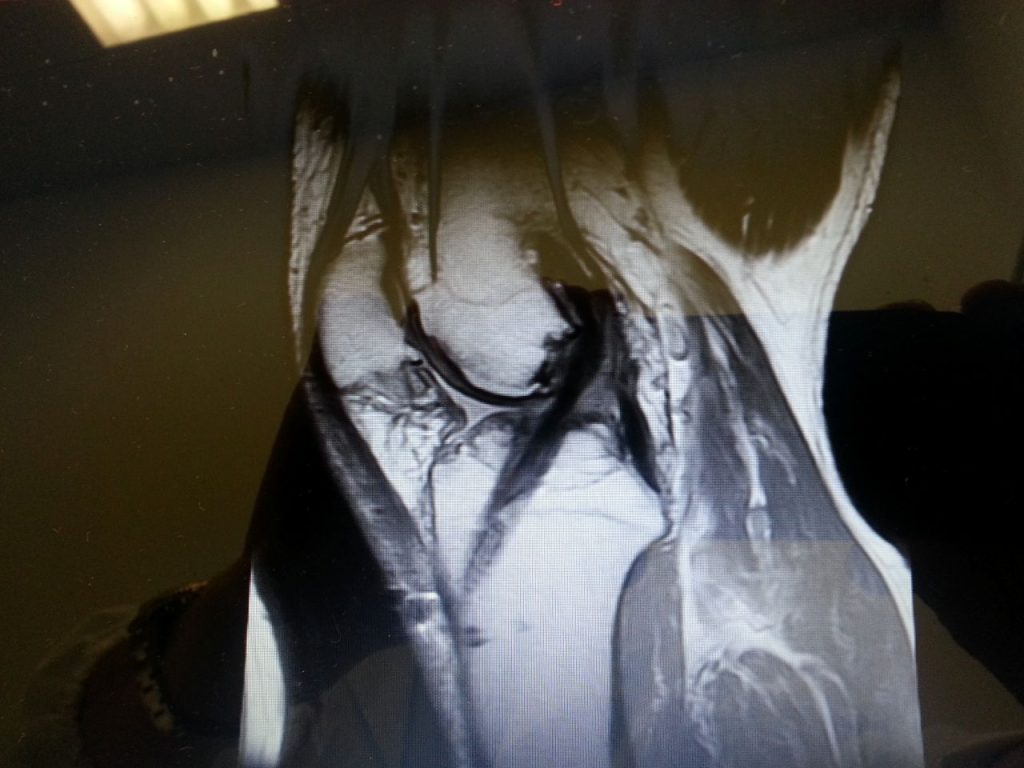

Chirurgia Artroscopica

• Ginocchio (menisco, cartilagine, LCA/LCP, legamenti collaterali)

• Spalla (cuffia dei rotatori, conflitto subacromiale, instabilità)

• Anca (cercine acetabolare, FAI, core decompression)

• Caviglia (lesioni cartilaginee, osteofiti, sinovite)

• Gomito e polso (lesioni traumatiche e degenerative)